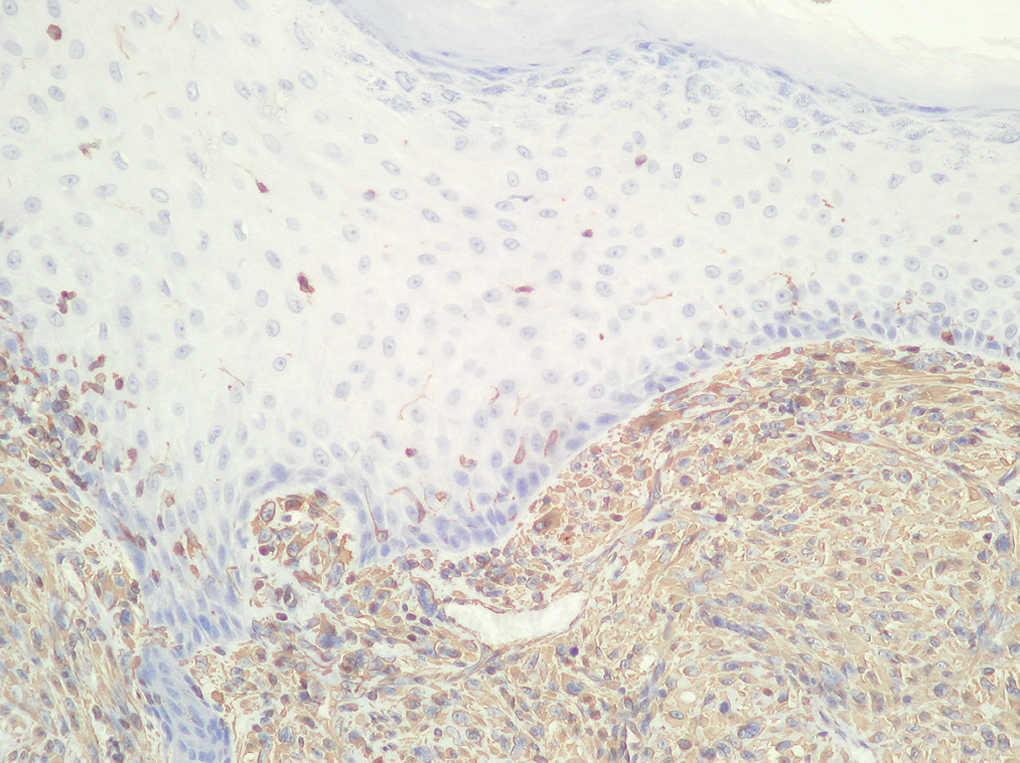

Fig. 3.--Estudio inmunohistoquímico. (Vimentina positiva.)

Neoformación de estirpe mesenquimatosa constituida por células de citoplasma y núcleo fusiforme, dispuestas en áreas y fascículos, entre las que aparecen células multinucleadas de cuerpo extraño (fig. 2), con focos de necrosis y elevada actividad mitótica. Las técnicas inmunohistoquímicas realizadas mostraron negatividad para actina, CD34, HMB45, EMA, CD68, CAM 5.2., desmina, pancitoqueratinas, S-100 y positividad para vimentina (fig. 3).

En el estudio inmunohistoquímico las células tumorales son vimentina positivas y presentan fuerte tinción para CD74 (LN-2). Puede demostrarse varios marcadores de histiocitos mediante el uso de la inmunoperoxidasa en un 60-80 % de los HFM. Los marcadores usados incluyen α1-antitripsina y α1-antiquimiotripsina. El CD68 (KP-1) es con frecuencia positivo, mientras que el CD34 suele ser negativo.